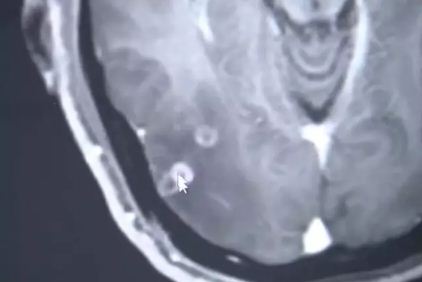

The infectious diseases department’s Dr. Wang Jian-rong was the one to treat Zhu as he told him about the symptoms. Dr. ran a few tests on him and finally found out what was living inside his body. The Doctor found out about 700 worms living in his body.

Well, they come from tapeworm eggs if you eat one or when we eat undercooked infected pork. The worms were found inside Zhu’s brain, his lunges and inside his chest too.